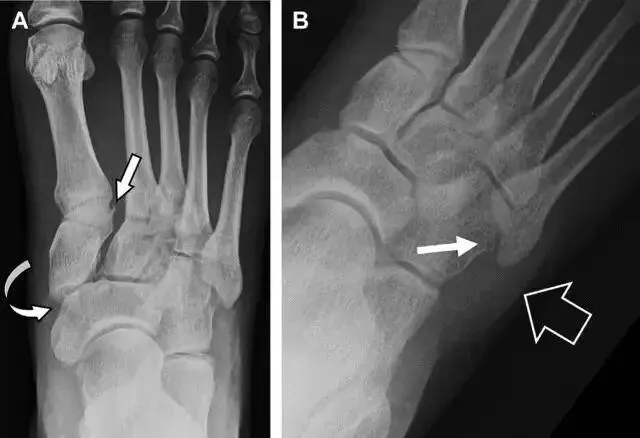

典型表现:第二跖骨底和内侧楔骨之间的骨折碎片,跖骨间间隙增宽,脱位亦可发生在舟骨-内侧楔骨关节,导致另一种变异的跗跖关节损伤(图A)。此外,骰骨的小块皮质撕脱在足部斜位片上可清晰显示(图 B)。

(图)从牛背上摔落的患者,跗跖关节骨折。A 正位片示内侧楔骨旁边的小骨折碎片(箭头),第二跖骨底向外半脱位;B 负重位侧位片示第二跖骨相对中间楔骨向背侧轻微移位(长方形);C-STIR 序列 MRI 图像示跗跖关节韧带断裂(箭头),第一至第三跖骨、内侧楔骨及中间楔骨均骨髓水肿。

(图)变异的跗跖关节骨折。A-另一种类型的跗跖关节损伤,中间楔骨向内侧半脱位(弧形箭头),从而使第一、第二跖骨间间隙变宽,需注意,骨折在靠近内侧楔骨处(箭头);B-外侧跗跖关节损伤伴随从骰骨跖骨韧带的骰骨撕脱(箭头),需注意,第五跖骨底近端处存在软组织水肿(空箭头)。